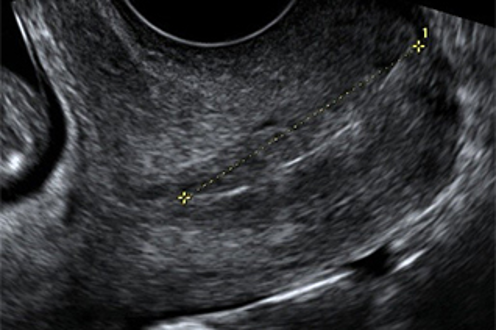

La Cervicometría, o ecografía para medición de la longitud cervical, se realiza por vía transvaginal. Consiste en la medición de la longitud del cuello del útero que es un indicador confiable del riesgo de parto prematuro. Su medición está indicada ante la presencia de contracciones uterinas y amenaza de parto antes del término.